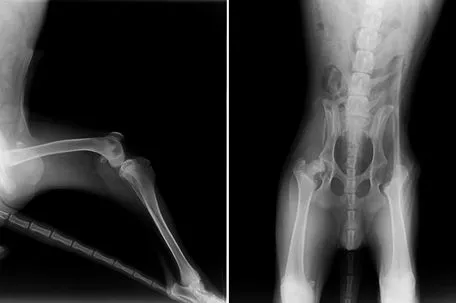

Pfotenhilfe-Geschäftsführerin Johanna Stadler: "Ich war schockiert, als mir das gepeinigte Hundekind übergeben wurde. Der Täter musste Leo immer wieder mit harten Gegenständen ins Gesicht geschlagen haben, denn dieses war komplett zugeschwollen. Am Hals hatte er Würgespuren und die Haut war mit blauen Flecken übersät. Leo humpelte auch auffällig, und auf den Röntgenbildern kann man erkennen, dass er offenbar so brutal misshandelt wurde, dass er sogar an der Hüfte operiert werden musste. Der junge Schäferhund war auch stark abgemagert und in einem extrem schlechten Gesamtzustand, und er erholt sich bis heute körperlich nur sehr langsam. Noch schlimmer sind aber seine seelischen Wunden, weshalb ich ihn persönlich rund um die Uhr betreue und tröste. Es ist mir unbegreiflich, wie man sich so skrupellos und brutal an einem Kind vergehen kann und mir kommen jetzt noch die Tränen, wenn ich daran denke, was Leo monatelang ertragen musste."